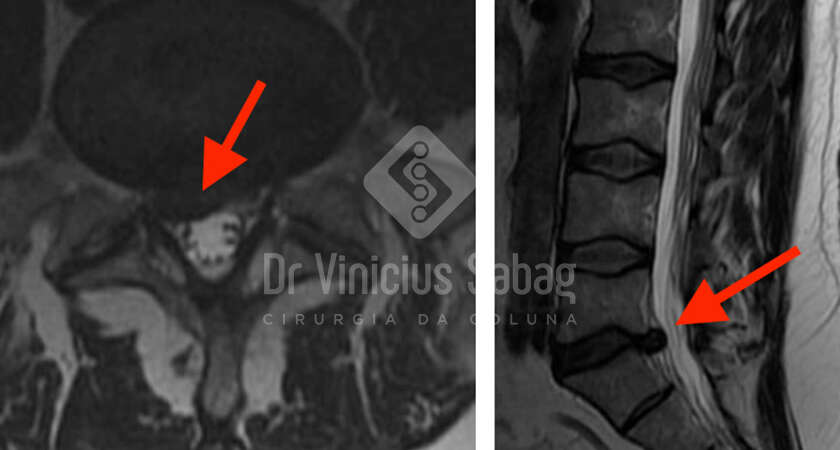

Paciente do sexo feminino, 58 anos, com queixa de dor lombar crônica associada à irradiação para ambos os membros inferiores há mais de três anos. O quadro apresentava caráter progressivo, com impacto significativo nas atividades diárias e na qualidade de vida.

Tratamento Conservador sem Resultado

Ao longo desse período, a paciente foi submetida a diversas…